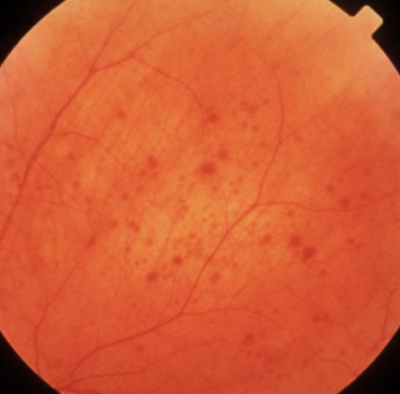

- Diabetic Retinopathy: Characterised by microaneurysms, haemorrhages, and swelling in retinal blood vessels.

Early detection through diabetic retinopathy screening and macular degeneration detection significantly reduces the risk of vision loss.